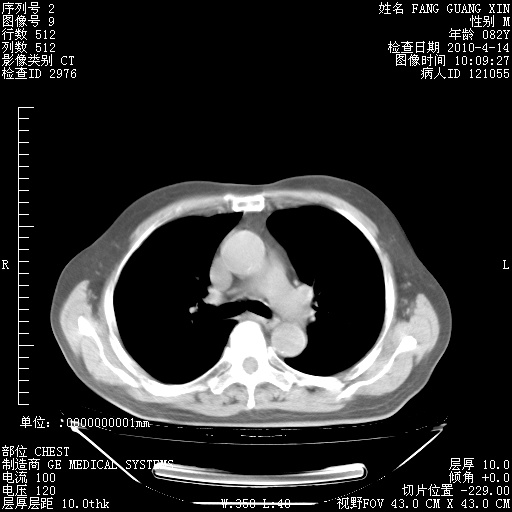

4月14日肺部CT

肺部CT平扫未见异常。